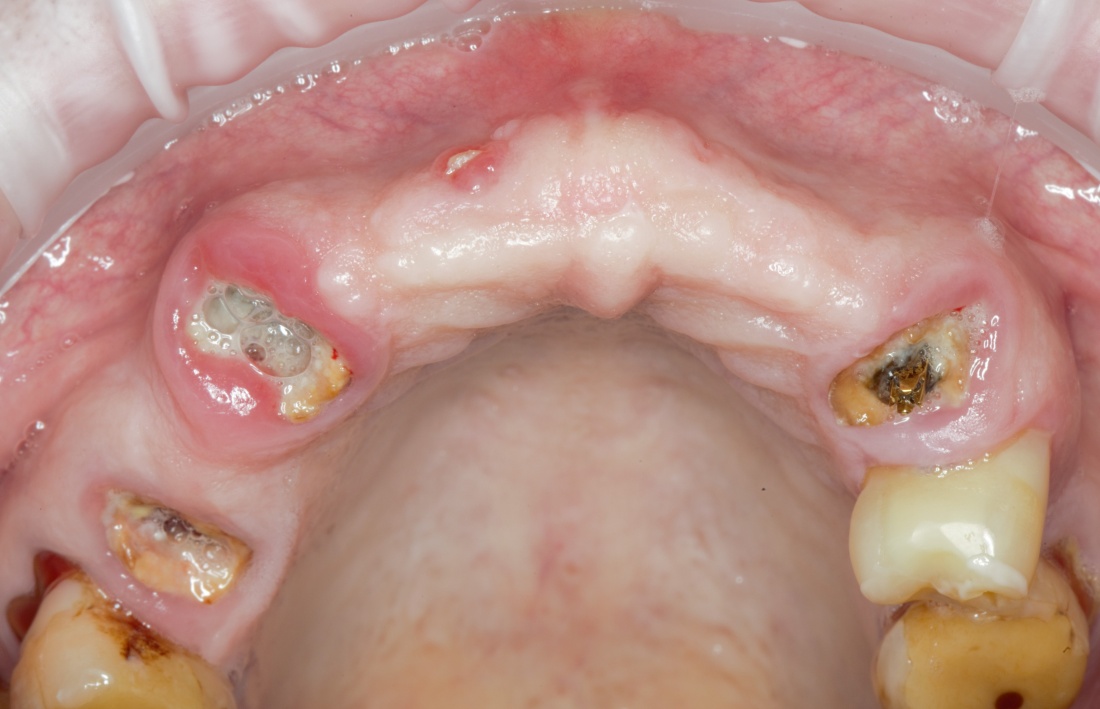

— вертикальная или горизонтальная атрофия костной ткани верхней или нижней челюстей, концевые или включённые дефекты.

— III или IX биотип костной ткани — идеальны. С I и II биотипом придётся повозиться

— мы имеем дело с атрофией как по высоте, так и по ширине альвеолярного гребня,

— работаем с I или II биотипом костной ткани,

— костной ткани «вааапще не осталось». Ну прям вааапще-вааааапще.

Например, в таком случае:

я бы зассал делать остеотомию предпочёл бы другой метод остеопластики